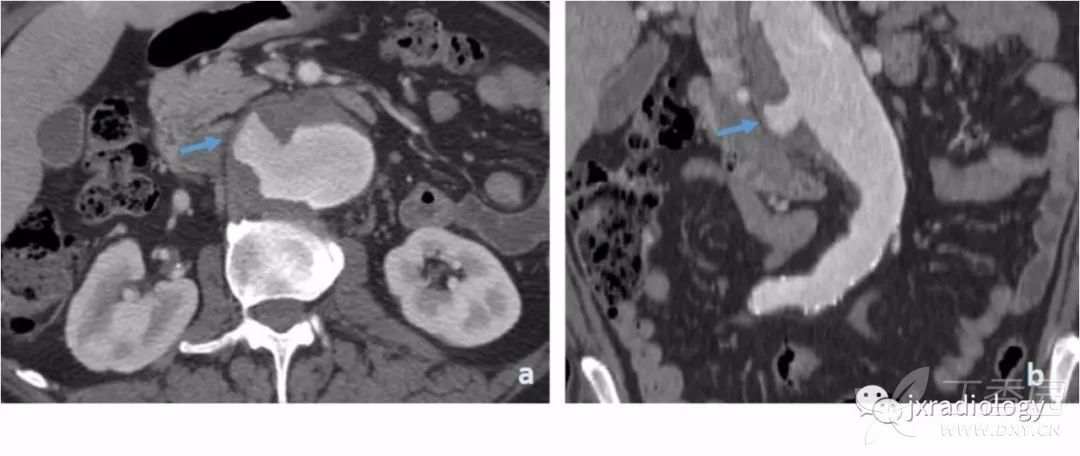

平扫CT上显示广泛的动脉粥样硬化通常是PAU患者的一个特征。注射对比剂后,主动脉壁出现不规则边缘和围绕溃疡基底部的内膜钙化提示PAU诊断( 图13 )。

图13:在轴位非增强CT显示主动脉后壁广泛的动脉粥样硬化(a图中箭头)。注射对比剂后,没有内膜瓣的情况下主动脉的后囊袋状突起(b和c图的星号)。

当发生破裂时,很难区分破裂的是动脉瘤或复杂的动脉粥样硬化性溃疡。在这两种情况下,都需要立即进行手术治疗。非穿透性溃疡一般限于内膜并常常无症状( 图14 )。

图14:非穿透性溃疡的患者。

血栓伴局灶性溃疡(a和b图的箭头),但没有对比剂超出内膜,也不存在壁内血肿。病人无症状。